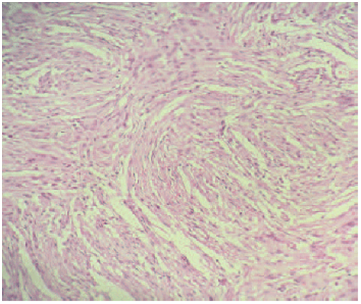

A 15years old girl, consulting for severe headache, with vomiting, and diplopia. The physical examination shows no motor or sensory deficit, and right 6th nerve pulsy, with papillary oedema grade 2. CT and MRI show a very large intraventricular tumor, located at the right lateral ventricle (Figure 3) (Figure 4). The patient underwent ventricular shunting, and the tumor was removed in a second time. The excision was total using a temporo parietal approach, and the post operative status was simple, with improvement of the headache. The histological exam indicates a fibroblastic meningioma too.

Figure 4 Axial CT with contrast enhancement , illustrating a large intraventricular meningioma.